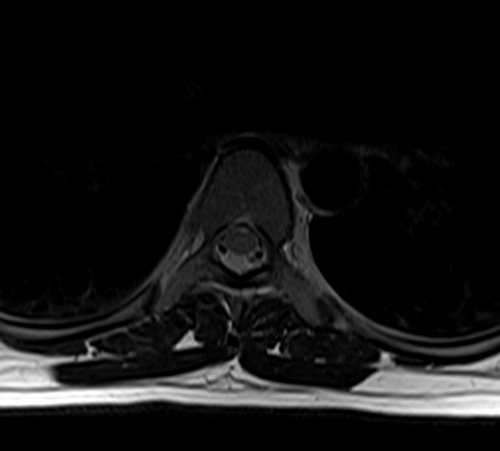

- МРИ грудного отдела позвоночника